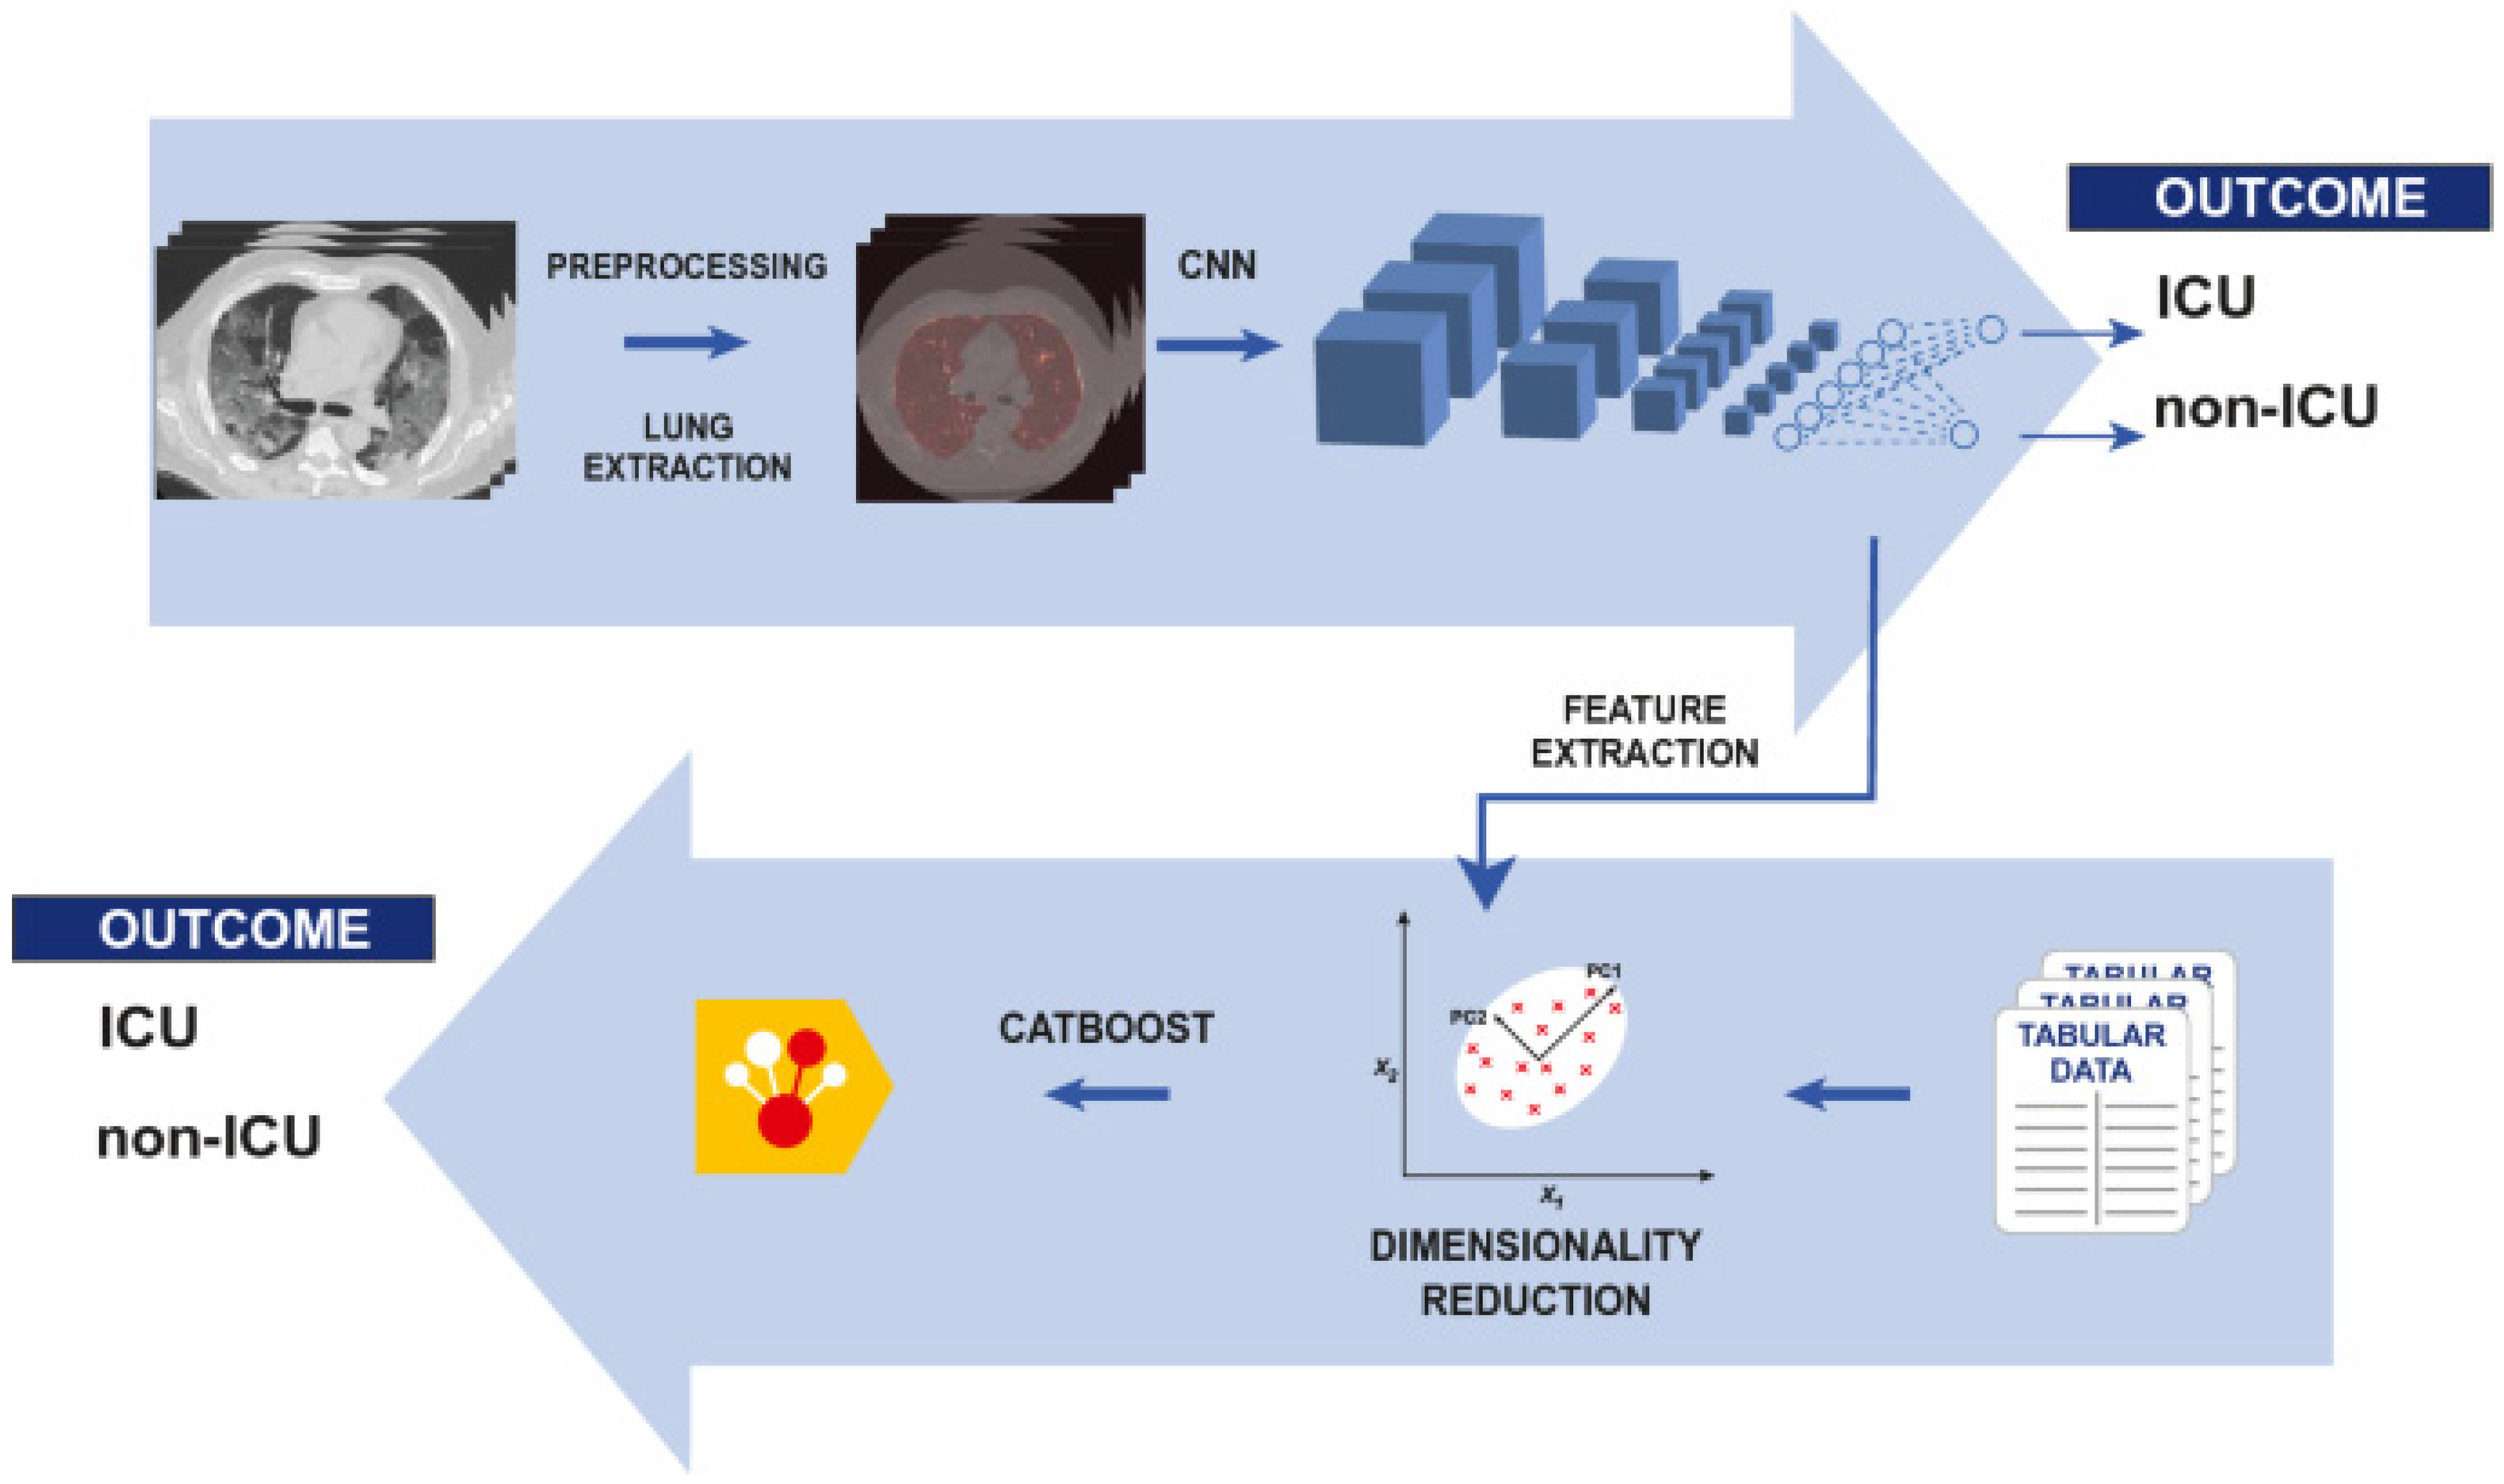

Medical Images for AI COVID-19 Diagnosis

CT and X-ray Medical Images for COVID-19 Diagnosis

Machine Learning (ML) and Deep Learning (DL) for COVID-19 Diagnosis

- Chieregato, M.; Frangiamore, F.; Morassi, M.; Baresi, C.; Nici, S.; Bassetti, C.; Bnà, C.; Galelli, M. A hybrid machine learning/deep learning COVID-19 severity predictive model from CT images and clinical data. Sci. Rep. 2022, 12, 4329. [Google Scholar] [CrossRef]